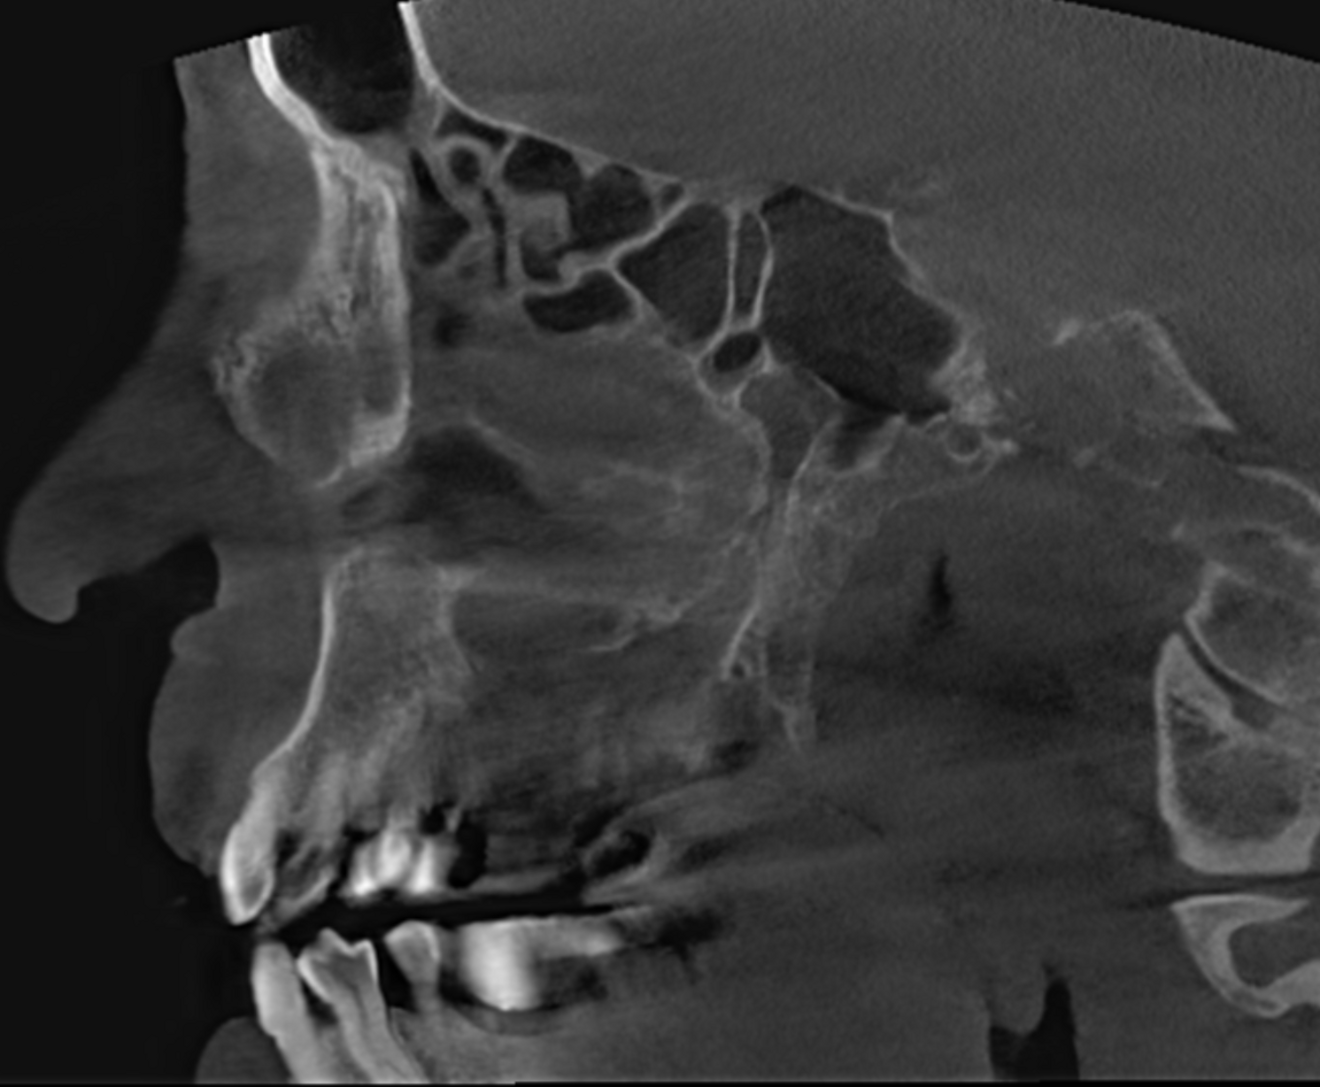

Fig. 2a: Large-volume CBCT scan, sagittal cross-section of the buccal roots.

Fig. 2b: Large-volume CBCT scan, sagittal cross-section of the palatal root.

The extent of the inflammation was shocking (Figs. 2a & b). Not only the maxillary sinus (Fig. 3) but the ethmoid and sphenoid sinuses too were involved, and the inflammation had spread towards the right cavernous sinus as well (Fig. 4). At this point, extraction may have been the first choice for most dental clinicians, but we had to keep in mind that invasive treatment may have increased the risk of cavernous sinus thrombosis, a potentially avoidable possibility. There are very few circumstances under which a dental procedure can cause very severe or even lethal consequences, but this case approached such a situation.